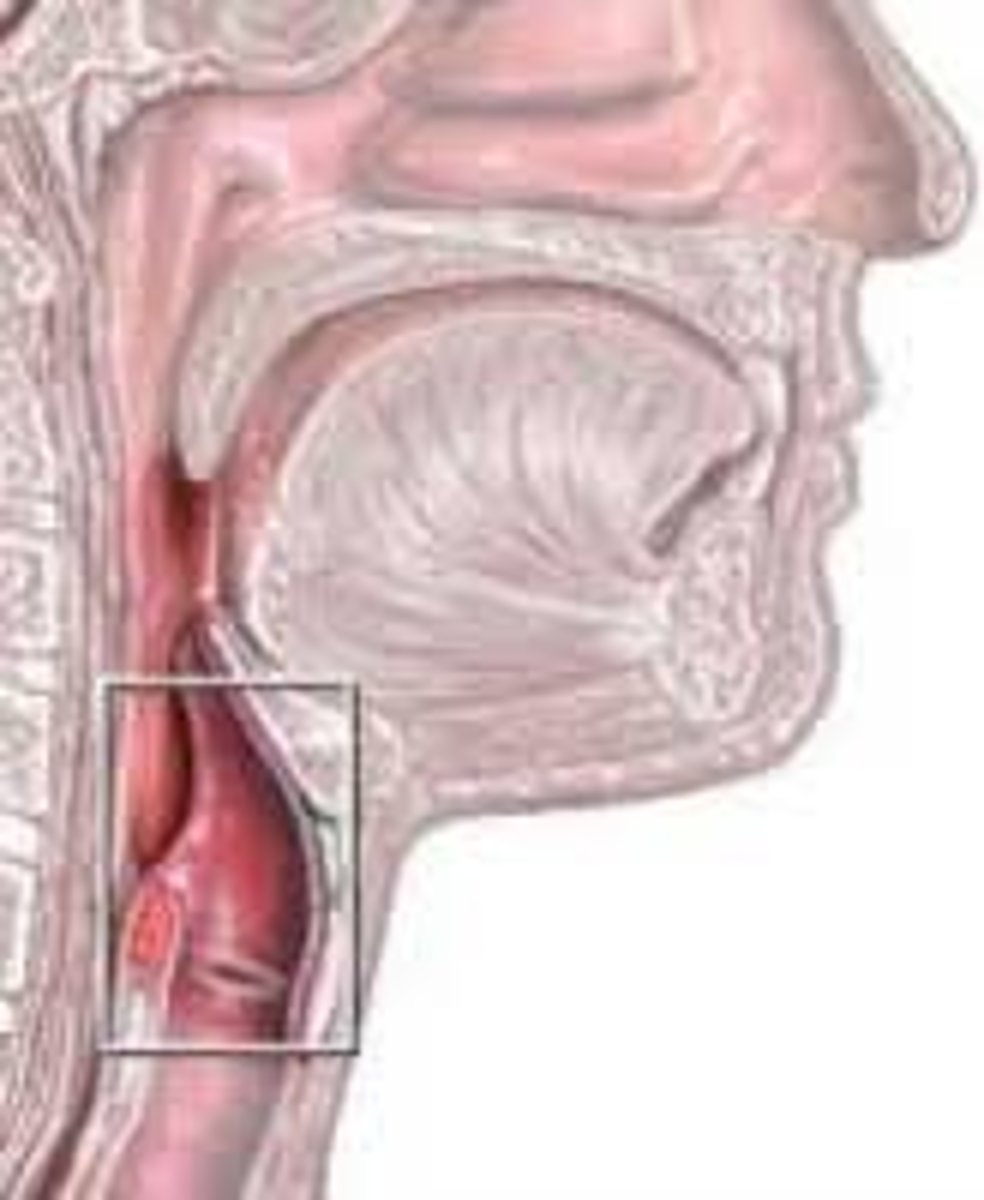

Larynx

Voice box; passageway for air moving from pharynx to trachea; contains vocal cords

Laryngeal Cartilages

Largely construct the larynx (voice box)

Thyroid Cartilage

A firm prominence of cartilage that forms the upper part of the larynx; the Adam's apple

Cricoid Cartilage

The ring-shaped structure that forms the lower portion of the larynx

Vocal Folds

Mucosal folds that function in voice production (speech); also called the true vocal cords.

Epiglottis

A flap of cartilage at the root of the tongue, which is depressed during swallowing to cover the opening of the windpipe

Trachea

A large membranous tube reinforced by rings of cartilage, extending from the larynx to the bronchial tubes and conveying air to and from the lungs; the windpipe.